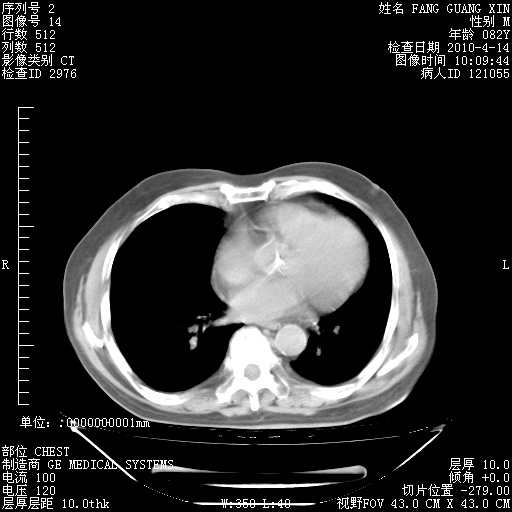

楼主| 发表于 2010-4-28 16:59 | 显示全部楼层

4月28日肺部CT——再次出现类似去年5月9日——透光度降低,(影像科认为)“间质性”改变。

1221483 1 .bmp

1221483 2 .bmp

1221483 3 .bmp

1221483 4 .bmp

1221483 5 .bmp